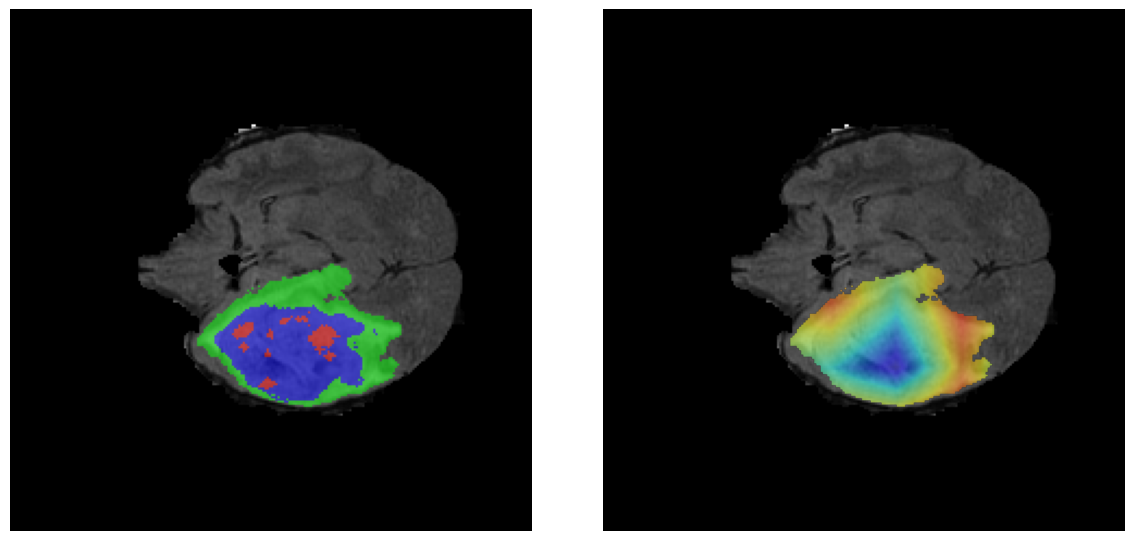

Mapas de Explicabilidad (Grad-CAM++)

Visualización de las regiones de atención del modelo que validan su razonamiento clínicamente relevante

Ejemplos HGG - Atención en Núcleo Necrótico y Tumor Realzado

HGG Grad-CAM++ 1 HGG Grad-CAM++ 2 HGG Grad-CAM++ 3 HGG Grad-CAM++ 4 HGG Grad-CAM++ 5 HGG Grad-CAM++ 6

Los heatmaps muestran que el modelo concentra su atención en las regiones de Tumor Realzado (rojo) y Núcleo Necrótico (azul), características patológicas clave de los gliomas de alto grado.

Ejemplos LGG - Atención Difusa en Edema Peritumoral

LGG Grad-CAM++ 1 LGG Grad-CAM++ 2 LGG Grad-CAM++ 3 LGG Grad-CAM++ 4 LGG Grad-CAM++ 5 LGG Grad-CAM++ 6

Para casos LGG, la atención del modelo es más difusa y se concentra principalmente en la región de Edema Peritumoral (verde), consistente con la naturaleza más infiltrativa y menos agresiva de estos tumores.